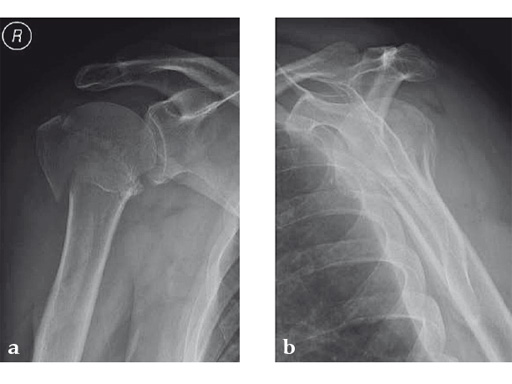

Case 2: Three-part valgus displaced fracture of the proximal humerus in a 63-year-old man.

The tuberosities have been reduced and fixed using intertubercular sutures (Fig 4). To reconstruct the medial support a calcar screw has been used. This determines the height of the nail. Therefore a 1 cm end cap has been used to get support for the proximal end of the nail in the part of the bone with the best bone quality.